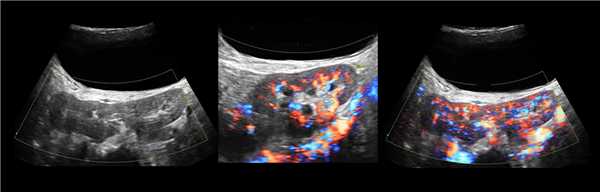

Состояние почечного кровотока

Для визуализации почечных кровеносных сосудов используют дуплексное сканирование (или допплерографию), при котором УЗИ-сканер выдает информацию в виде цветного изображения или спектрального графика. Методика является неинвазивной и безболезненной.

Исследование позволяет определить состояние сосудистой стенки, наличие внутрисосудистых обструкций и стенозов, определить скорость кровотока. В норме скорость может колебаться от 50 до 150 см/сек.

На цветовой схеме нормальными считаются темные тона. Яркий цвет фиксирует ускоренный кровоток и свидетельствует о наличии стеноза, основным признаком которого считается усиление кровотока в почечной артерии больше 200 см/сек.

Определяется индекс сопротивления кровотока или индекс резистентности, который напрямую зависит от возраста пациента: чем старше, тем выше скорость кровотока и выше индекс. В норме индекс сопротивления для почечной артерии - 0,7, для междолевых артерий - 0,34-0,74.